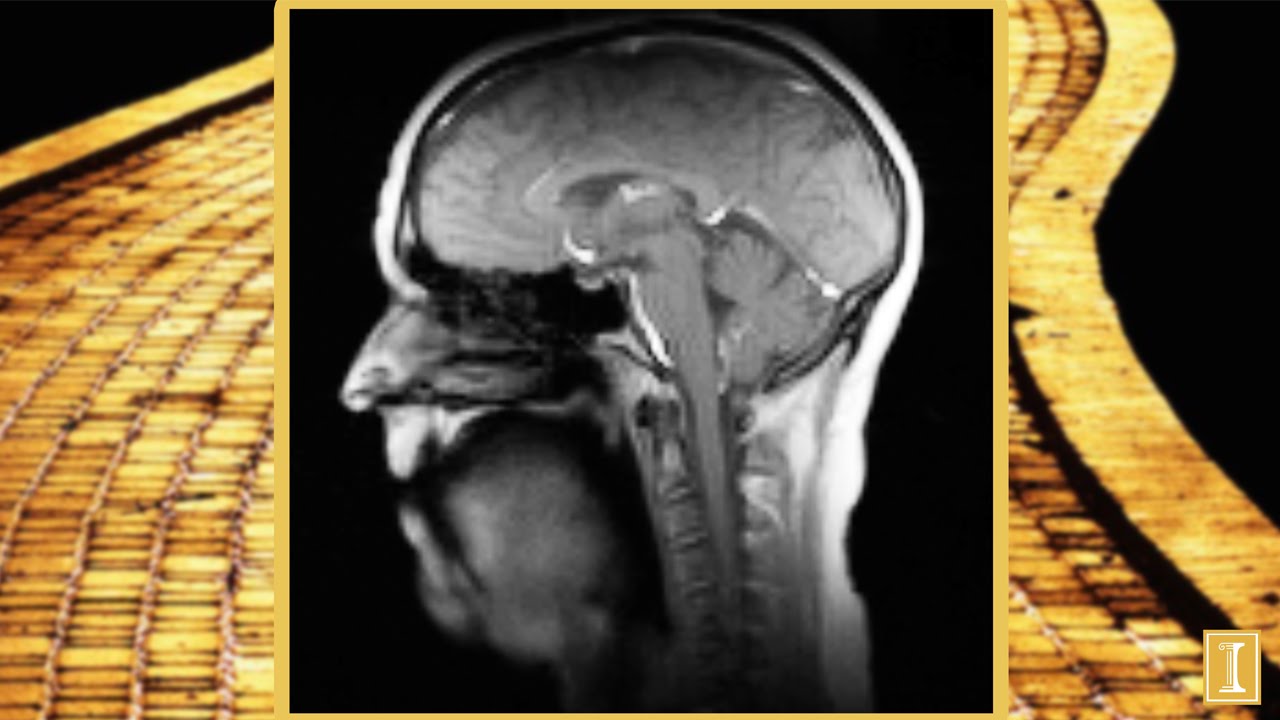

Normally, you have to stay absolutely still during an MRI, but researchers wanted to try a new technique that is 10-times faster than standard MRI scanners to illustrate how the hundreds of muscles in our neck, jaw, tongue, and lips work together to produce sound. The overall goal of the research is to see if singing in a group chorus can help people in retirement homes build stronger voices. Sounds like a worthy endeavor to me!